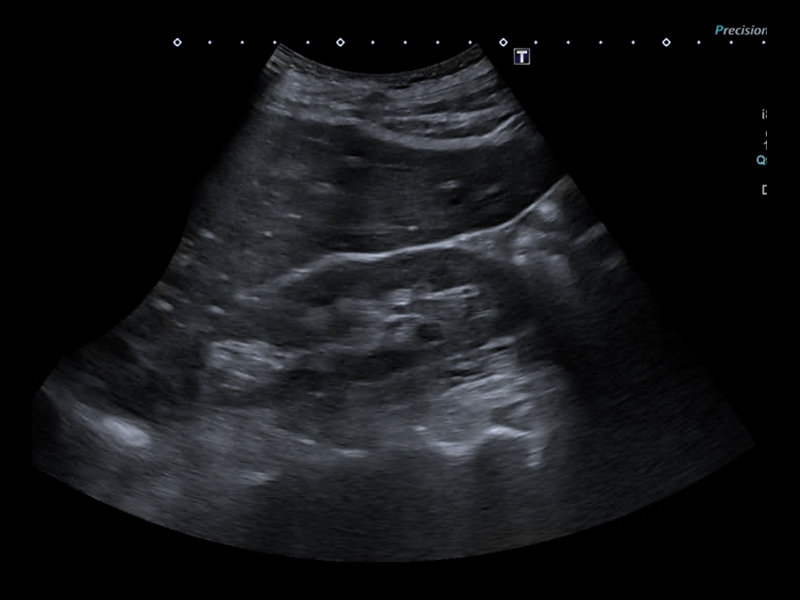

Ultrazvukové vyšetření radiologem

- pavilon B3 nebo B5

- lačnost

- žádanka vystavena elektronicky